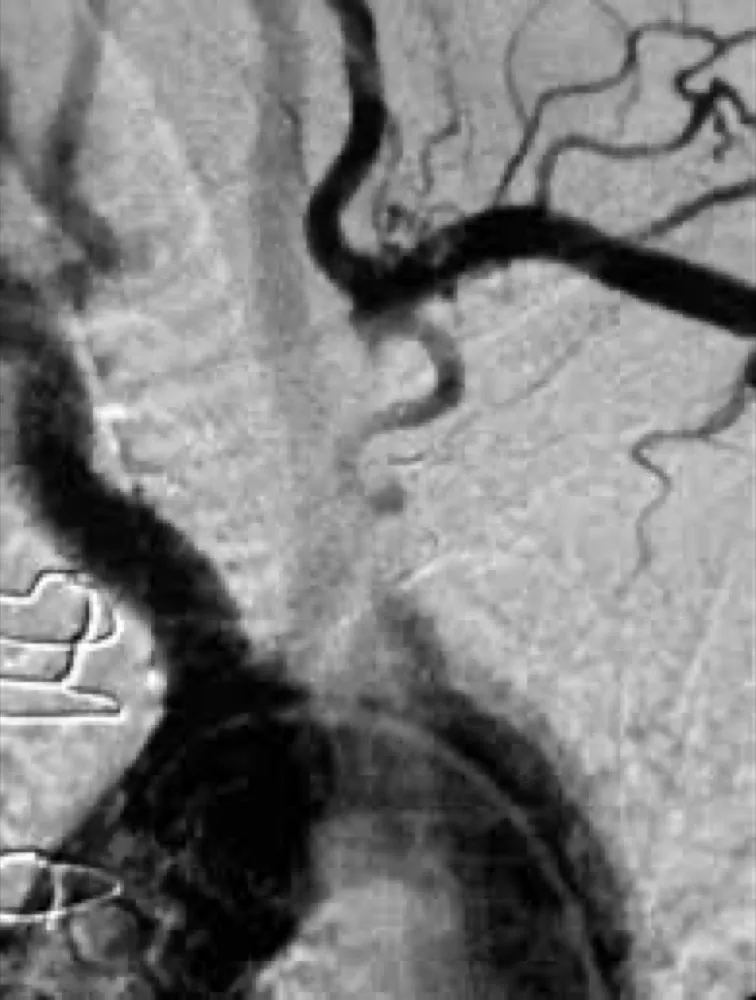

Paciente dislipidêmica, 47 anos, tomando suplemento "natural" para colesterol. Nenhuma queixa renal — até a creatinina chegar em 4.26. O agente não era uma droga controlada. Era arroz vermelho fermentado. E o rim foi o alvo.